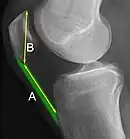

The Insall-Salvati ratio helps to indicate patella baja on lateral X-rays, and is calculated as the patellar tendon length divided by the patellar bone length. An Insall-Salvati ratio of < 0.8 indicates patella baja.[6]

- 1 2 Douglas Dennis (2017-02-25). "TKA in Patella Baja (Infera)". Orthobullets. Retrieved 2019-02-08.